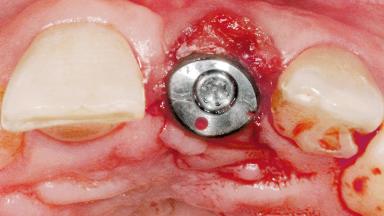

Late Flapless Placement of an Implant in a Maxillary Left Central Incisor Site

A 39-year-old male patient presented with a chief complaint of discomfort and gingival discoloration around his maxillary left central incisor. He was in good general health and was a non-smoker. His past dental history was significant because of the traumatic fracture of tooth 21 in a sporting accident at age 13. Initial dental treatment included endodontic therapy and a full-coverage restoration. The patient became symptomatic 5 years later, when structural failure of the tooth resulted in the dislodgment of the crown. Endodontic retreatment, apical surgery, and post-and-core restoration were performed.

Type of Implants One-Piece

Bone Augmentation Horizontal|Staged

Soft Tissue Grafting Simultaneous